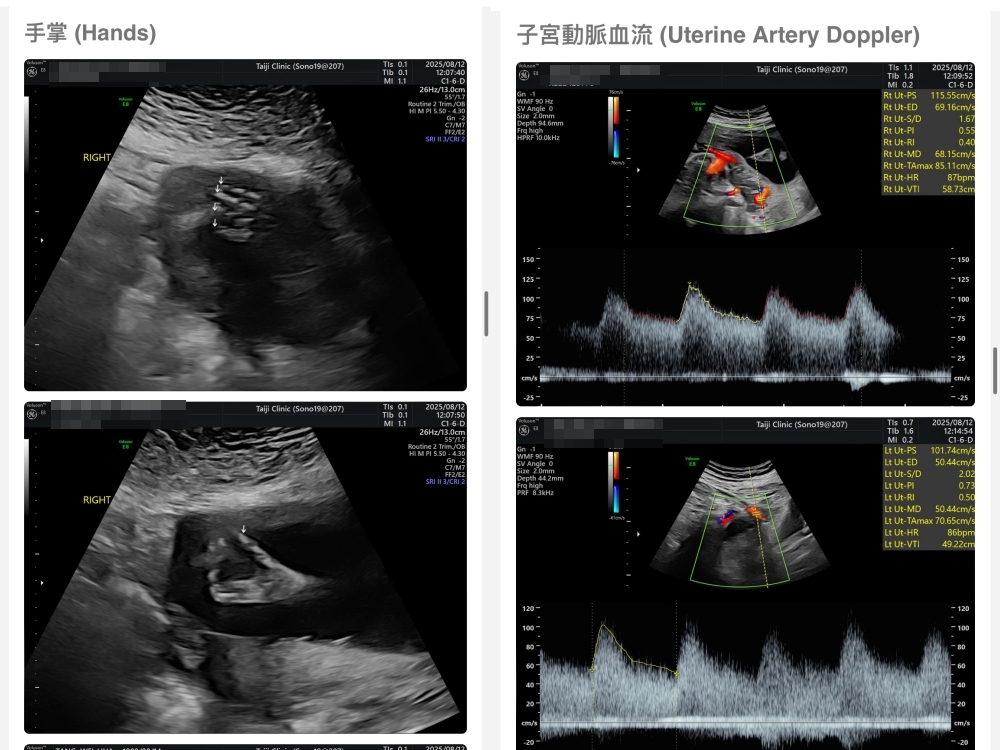

【台兒|高層次超音波|檢查結果】

▲離開診所後會收到MAIL,我們14:05離開,大約是16:45收到mail,裡面會有滿滿的超音波照片,紀錄的很詳細!也會提供紙本的報告,可以給日後產檢的醫師做參考👌